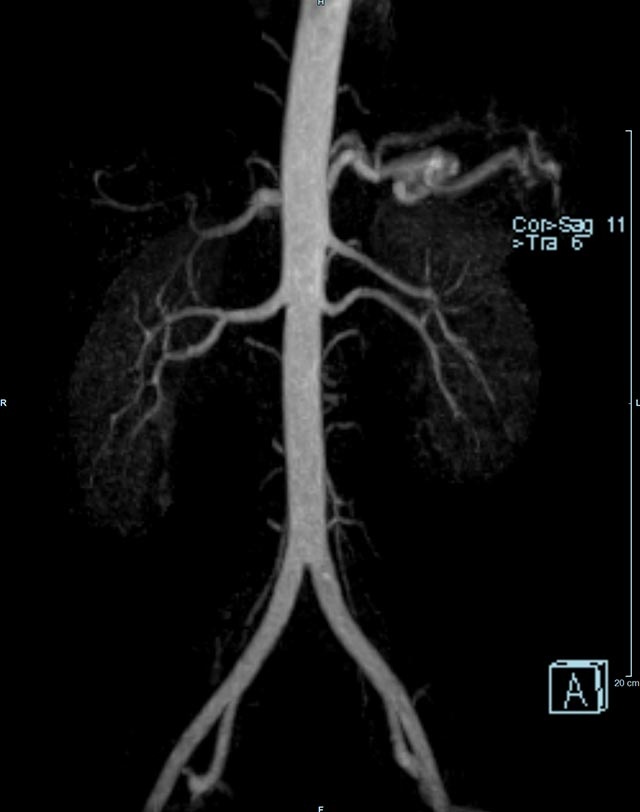

• Bauchgefäße

• Erfassung und Verlaufskontrolle bei arteriellen Aneurysmen (Aussackungen der Arterien), vor allem der Bauchaorta

• Darstellung von Gefäßengen an Nierenarterien, Baucharterien und Becken-/Beinarterien

MR-Angiografie (MRA)

• MR-Angiographie mit Kontrastmittel

• Erfassung arterieller und venöser Gefäße/Bypässe aller Körperregionen mit 3D-Rekonstruktion